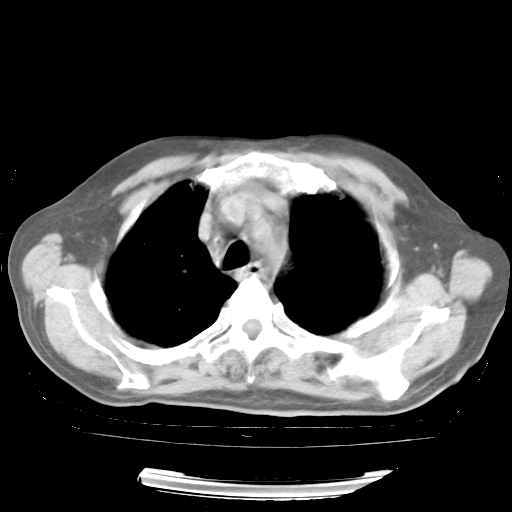

今天部分检查

轻微咳嗽,无痰,(体温正常时)R20次/分,P75次/分,双肺底、腋下可闻及少量捻发音。下肢轻度浮肿。

血常规:白细胞9.11×109/L,N0.92,L5.64,血小板39.2×109/L,HB148g/L,ESR2mm/H。

尿常规:潜血+

血生化:总蛋白69.71g/L,白蛋白38.40g/L,球蛋白31.31g/L,CRP27.9mg/L,尿素氮11.98mmol/L,肌酐106μmol/L,乳酸脱氢酶1099 U/L,肌酸激酶108U/L,CK-MB 61U/L。

腹部B超:胆囊壁增厚,肝、胆、胰、脾、肾无异常,肠系膜淋巴结、腹膜后淋巴结无增大。

ECG:右心室增大

心脏超声检查:无右心室增大。

增加治疗:异烟肼、利福平、乙胺丁醇,静滴左氧氟沙星、参麦注射液。甲强龙从80mg暂减为40mg。

强的松3月1日改为10mg qd,4月1日改为10mg qod。3月份以前的减量过程和环磷酰胺疗程需等明天查看记录(我岳父自己做的记录在他家里)。